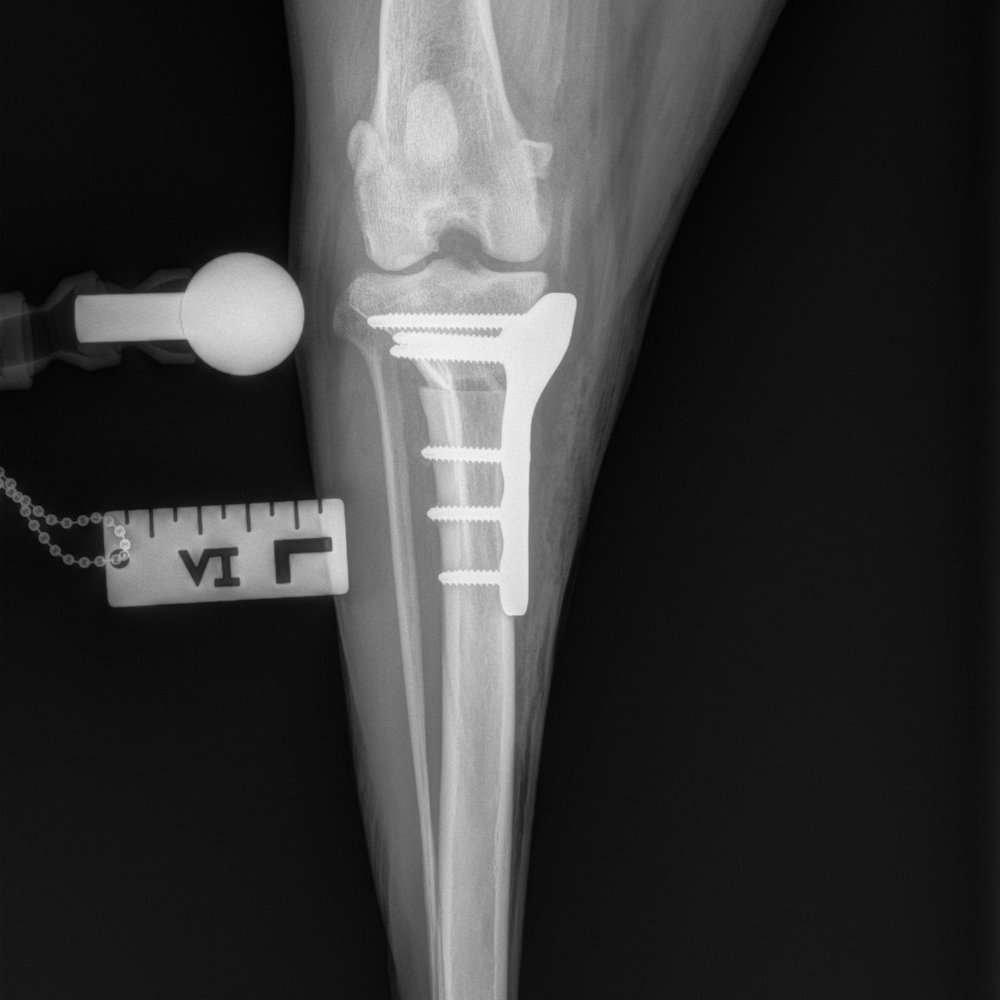

The RITA LEIBINGER Titanium TTA RAPID® Tiny, 2.0/2.4 TPLO and Titanium TPLO Swing, and our 2.0/2.4 Titanium CBLO implant systems and instrumentation are specifically designed for small patients, and can help overcome these challenges. They are typically smaller in size and have different geometries to accommodate the smaller bone structure of small dogs and cats.